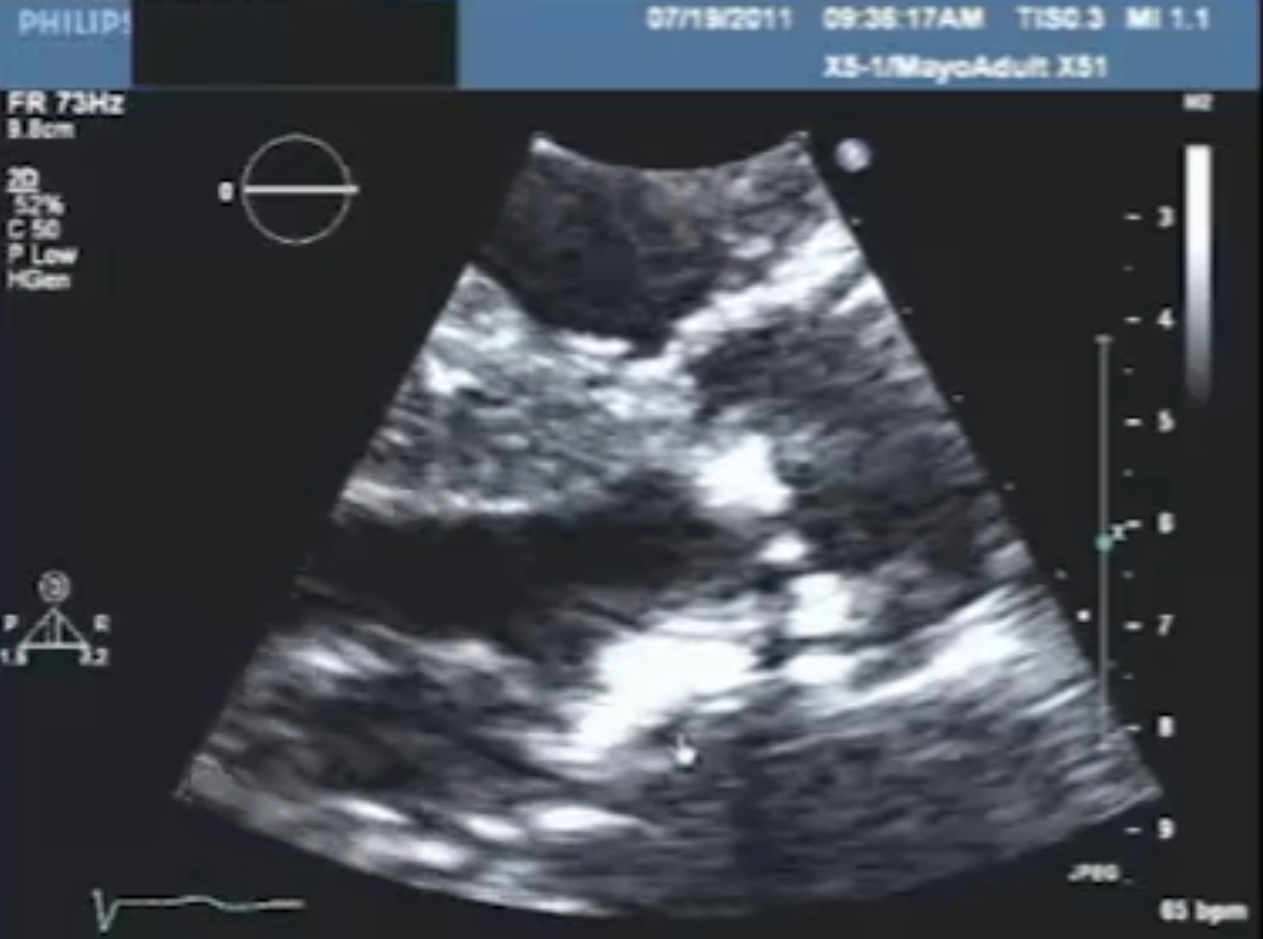

Diagnosis

Radiation MS